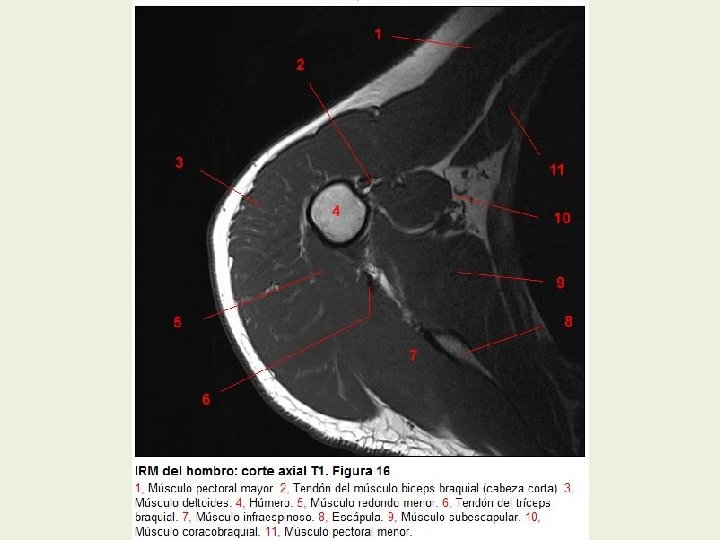

Hombro Cortes axiales RMN